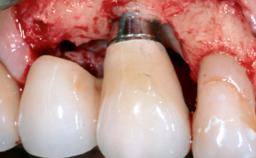

Occlusal Load—a Factor for Implant Failure?

In this case, Nicola Zitzmann describes the sudden loss of a previously well-osseointegrated implant that had been in healthy function for 5 years. The case includes recommendations for occlusion and function of implant restorations. A 74-year-old patient had received implant-fixed dental prostheses in the maxilla in 2008, and in the right mandible three years later. His tooth loss was mainly related to recurrent caries associated with hyposalivation as a potential side effect of his cholesterol-lowering medication.